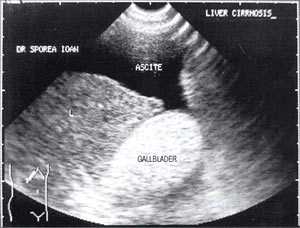

В исследовании, проведенном в США, "желчный сладж" выглядел в виде гиперэхогенного образования в желчном пузыре с горизонтальным уровнем без задней тени, форма которого медленно изменялась при движении больного [10]. Характерный признак "желчного сладжа" - изменение его вида на сканограмме в зависимости от изменения положения тела больного и медленным достижением нового горизонтального уровеня. Общим правилом является отсутствие дистальной акустической тени. Эхогенность сладжа может быть различной. Иногда сладж заполняет весь желчный пузырь, затрудняя дифференцировку между тканью печени и желчным пузырем. Эта ситуация называется "гепатизация желчного пузыря" (рис. 1).

Рис. 1. Гепатизация желчного пузыря, полностью заполненного сладжем.

Рис. 4. "Желчный сладж" у больного с циррозом печени.

Рис. 5. Желчный пузырь, заполненный сладжем, у больного циррозом.